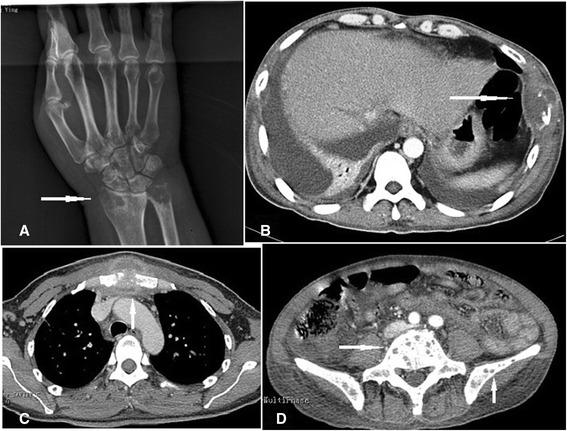

P. marneffei infection was diagnosed in 100 patients (65 HIV-infected and 35 HIV-negative). Fourteen patients, all HIV-negative, (14/35, 40%) had osteolytic lesions. The most common comorbidity was diabetes mellitus, though previous glucocorticoid therapy, β-thalassemia, breast cancer, and Langerhans cell histiocytosis also occurred. Five patients had no comorbidity. Fever, malaise, ostealgia, weight loss, and anemia were the most common symptoms, followed by cutaneous lesions, lymphadenopathy, hepatosplenomegaly, cough, sputum, and stethalgia. Ostealgia, joint pain, and joint disorders were also recorded. White blood cell and neutrophil counts were increased (mean 22.3 ± 7.4 × 10(9) cells/L; mean 18.84 ± 4.5 × 10(9) cells/L, respectively). The most common sites were the vertebrae, skull and femur, ribs and ilium, though the clavicle, scapula, humerus, and tibia were also involved. Radiography and computed tomography (CT) showed multiple radiolucencies with moth-eaten bone destruction, periosteal proliferation, bone fracture, and surrounding soft-tissue swelling. Emission CT showed significantly increased uptake in many skeletal regions. Positron emission tomography/CT showed generalized lymphadenopathy, bone metabolic activity, and bone destruction. The (18) F-FDG standard uptake value was increased in the entire skeleton (mean 6.16). Twelve patients received antifungal therapy, four of whom died during treatment, and eight recovered, though four of these eight relapsed within 3-24 months. Two patients discontinued treatment because of severe multiple organ failure and died.

100例患者确诊为马尔尼菲青霉感染(65例合并HIV感染,35例未合并HIV感染)。14例患者(均未合并HIV感染,14/35,40%)有溶骨性病变。最常见的合并症是糖尿病,不过既往糖皮质激素治疗、β地中海贫血、乳腺癌及朗格汉斯细胞组织细胞增多症也有发生。5例患者无合并症。发热、乏力、骨痛、体重减轻及贫血是最常见症状,其次是皮肤病变、淋巴结病、肝脾肿大、咳嗽、咳痰及胸痛。也记录到骨痛、关节疼痛及关节功能障碍。白细胞及中性粒细胞计数升高(分别平均为22.3±7.4×10⁹/L;平均为18.84±4.5×10⁹/L)。最常见部位是脊椎、颅骨及股骨、肋骨及髂骨,不过锁骨、肩胛骨、肱骨及胫骨也受累。X线摄影及计算机断层扫描(CT)显示多处透亮区伴虫蚀状骨质破坏、骨膜增生、骨折及周围软组织肿胀。发射型CT显示许多骨骼区域摄取明显增加。正电子发射断层扫描/CT显示全身淋巴结病、骨代谢活性及骨质破坏。全身骨骼的(18)F-FDG标准摄取值升高(平均为6.16)。12例患者接受抗真菌治疗,其中4例在治疗期间死亡,8例康复,不过这8例中有4例在3 - 24个月内复发。2例患者因严重多器官功能衰竭停止治疗并死亡。